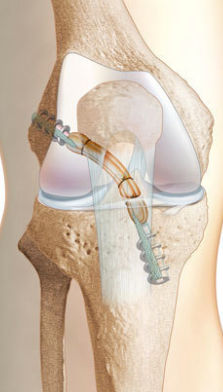

Chirurgie DIDT

L'intervention consiste à reconstruire le ligament rompu

Dr Dessyn Centre orthopédie Aubagne